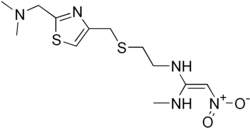

| Nom UICPA | N-(2-[(2-[(diméthylamino)méthyl]thiazol-4-yl)méthylthio]éthyl)-N-méthyl-2-nitroéthène-1,1-diamine |

| Formule | C12H21N5O2S2 [Isomères] |